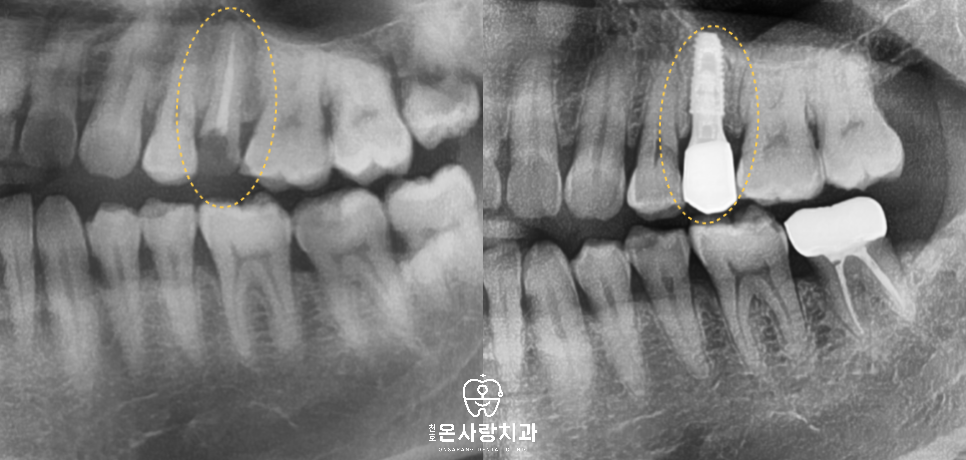

오른쪽 위와 왼쪽 아래의 큰 어금니는

깊은 우식이 있어 신경치료 후

크라운 수복을 진행했습니다.

가장 큰 문제는 오른쪽

아래 큰 어금니부위였습니다.

오랜 기간 보이지 않는 쪽에서

염증이 진행되면서 치조골이

뿌리 주변에 거의 남아 있지 않았고,

저작 시 심한 통증과 흔들림이 있어

두 번째 큰어금니는

발치가 필수였습니다.

발치 후 치조골 이식을 시행해

잇몸뼈를 회복시키고

임플란트를 식립하였으며

그로 인해 영향을 받았던

첫 번째 큰어금니는 치조골이

균형적으로 회복된 이후 신경치료와

크라운을 통해 보존할 수 있었습니다.

이와 별개의 문제로 기존에

신경치료가 되어 있던

왼쪽 위의 작은어금니는

치관이 거의 남지 않은 상태였고,

구조적으로 힘을 지지할 수 없어

천호역치과을 통해서 발치를 결정한 뒤

임플란트를 계획했습니다.

신경치료만 하고 크라운을 하지 않은

치아가 시간이 지나 파절되는

전형적인 형태였기에

신경치료 후 크라운의

중요성을 설명드리며 향후 같은

상황이 반복되지 않도록 안내했습니다.